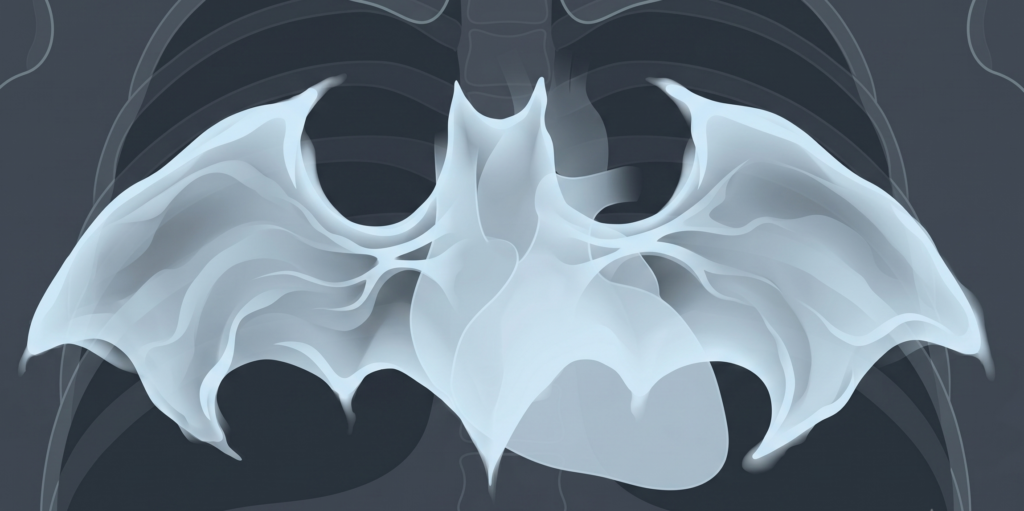

CHF Radiography—Beware the Batwings!

Findings correlate directly with increasing hydrostatic pressure—evolving from simple cardiac enlargement to life-threatening alveolar edema.